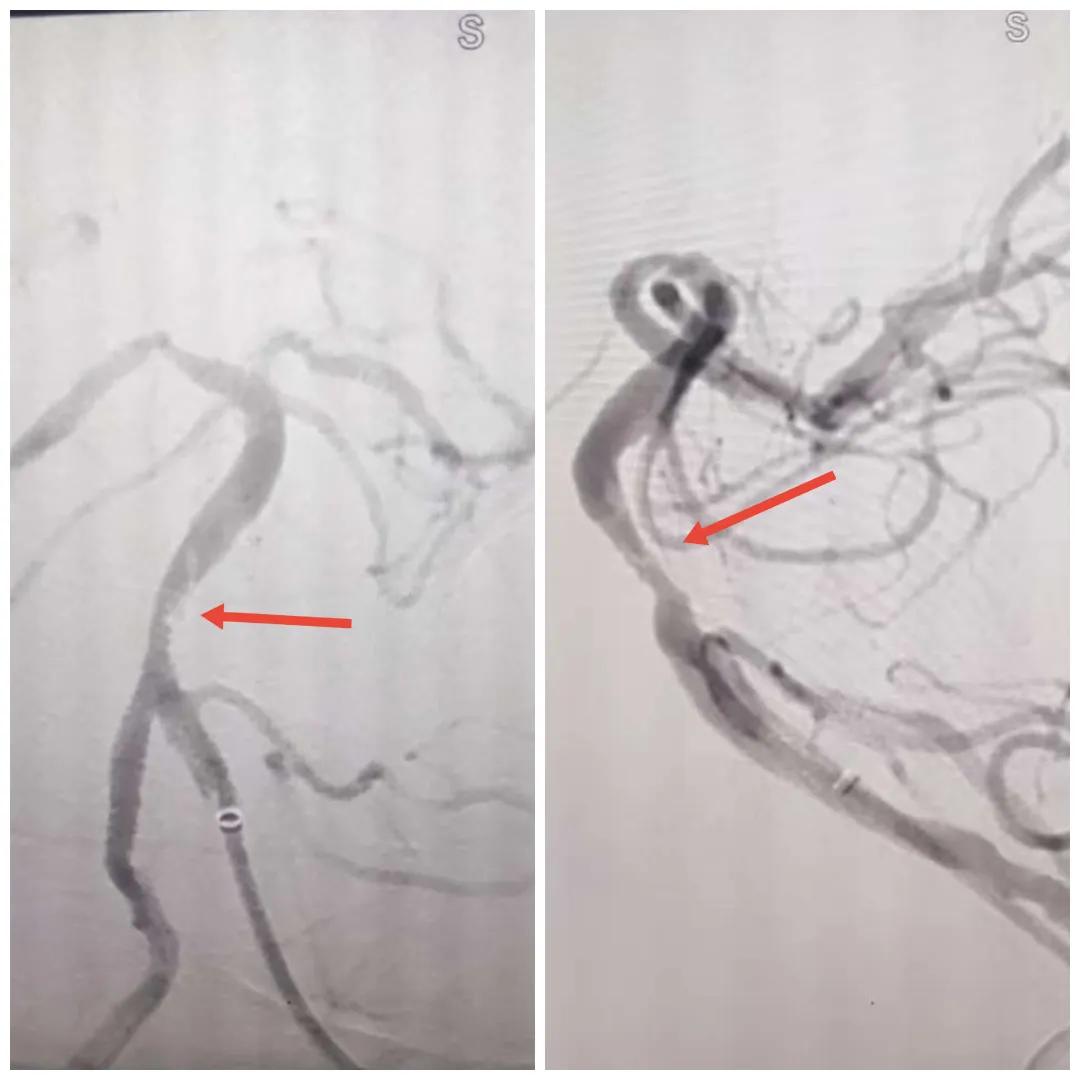

在經(jīng)造影后,主刀醫(yī)生腦一科副主任楊慶堂發(fā)現(xiàn)患者基底動脈下段重度狹窄且狹窄段以遠有大負荷血栓,其狹窄處考慮為動脈夾層,手術(shù)難度及風險較大。楊慶堂副主任在彭壯副主任醫(yī)師的協(xié)助下運用spaceman(太空人)技術(shù),中間導(dǎo)管抵近血栓抽吸配合支架拉栓,成功開通血管。再次造影可見基底動脈管腔明顯增寬,遠端血管顯影良好,且等待20分鐘后造影仍顯示血流通暢。楊慶堂副主任考慮到本次手術(shù)時間不宜過長,現(xiàn)患者基底動脈及分支前向血流維持良好,給予其抗栓藥物應(yīng)用后結(jié)束手術(shù),并建議患者3個月后復(fù)查造影,明確其基底動脈夾層情況。

取栓后血管管腔增寬,前向血流良好